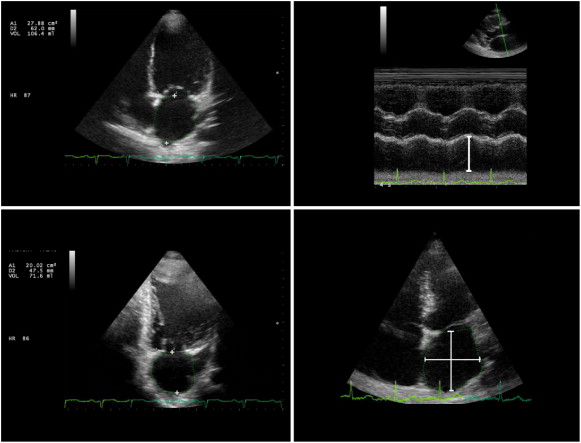

All patients were imaged in the left lateral position using an Esaote My Lab 5 Gold ultrasound system. Left atrial maximum volume (LA Vmax) was measured at LV end systole, LA minimal volume (LA Vmin) at LV end diastole and LA volume at the onset of atrial contraction (Vp) at the onset of electrocardiographic P wave from the apical four-chamber and apical two-chamber views using the biplane area–length method (Fig. 1) [11]. LA active emptying fraction ACTEF equals the difference between Vp and Vmin, divided by Vp i.e. ACTEF = (Vp-Vmin)/Vp [12] ;  [13].

Left; left atrial volume measured using biplane (apical four, upper, and two ...

Fig. 1.

Left; left atrial volume measured using biplane (apical four, upper, and two chamber, lower, views) area–length method. Right; left atrial antero-posterior (upper), superior–inferior and medio-lateral (lower) diameters.

LA antero-posterior dimension (D1) was measured at end systole in the parasternal long axis view from the trailing edge of the posterior aortic wall to the leading edge of the posterior LA [11]. The superior–inferior (D2) and medio-lateral dimensions (D3) were measured in the apical four chamber view at end systole (Fig. 1). We used left atrial eccentricity index (LAEi = {2 × D2} / {D1 + D3}) to assess the changes in the LA shape [14].